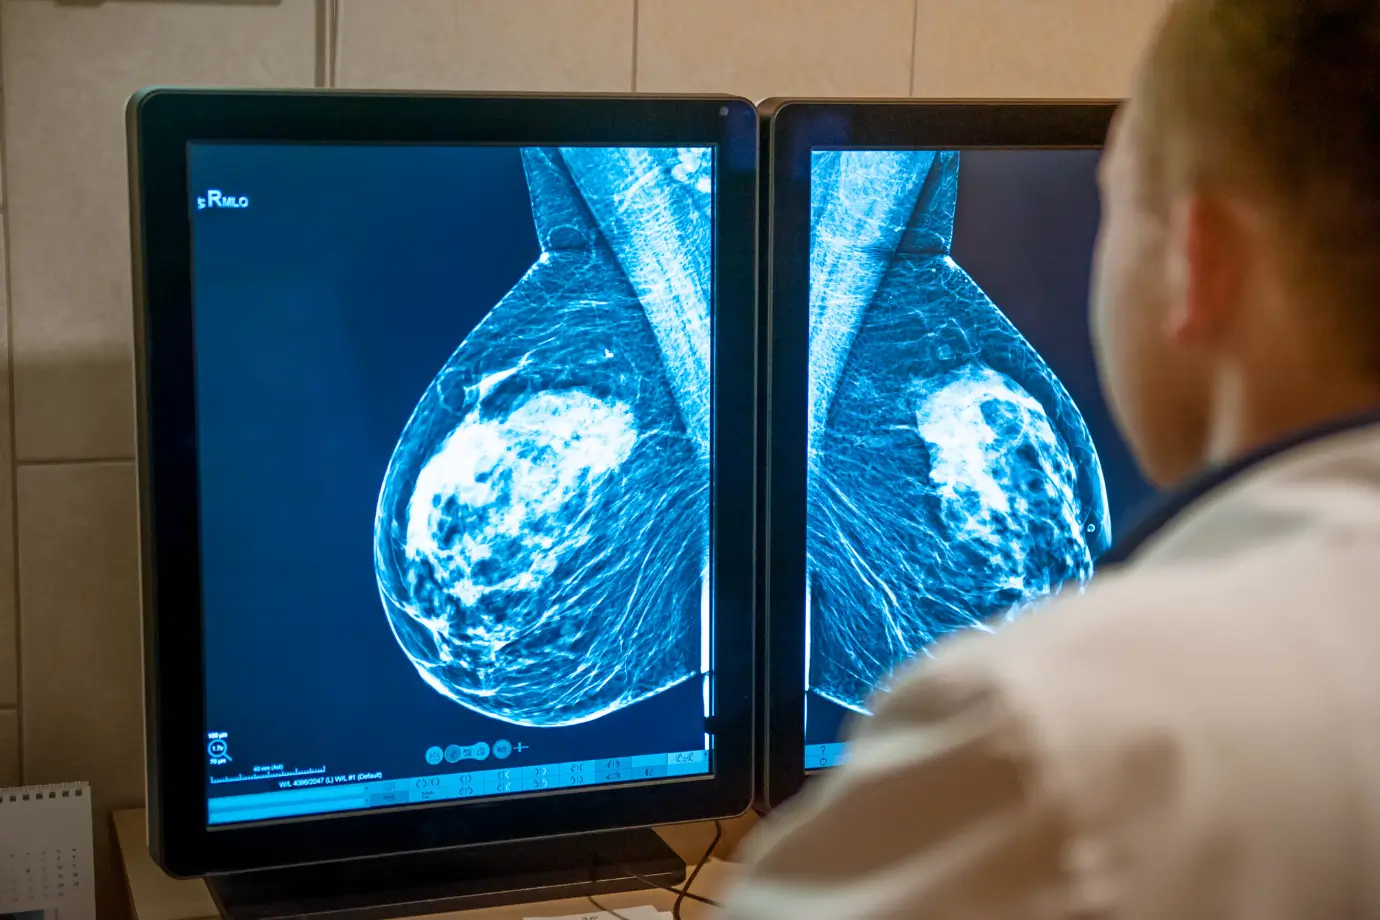

Mammography

Mammography is a well-established screening and diagnostic tool used to evaluate breast tissue for the possible presence of cancer through the use of low-dose X-rays.

The goal of mammography is to aid in the early detection of breast changes and doing so, improve prognosis.

We utilize tomosynthesis with our mammograms, which is an advanced form of mammography providing thin slice evaluation, improving detection rates, and reducing the need to perform additional mammographic views.

All our mammograms are followed by an ultrasound examination to allow for further analysis and, if necessary, lesion characterization.

All mammograms and ultrasounds are performed by trained mammographers and reviewed by a radiologist.

We follow international guidelines and recommend an annual mammogram from age 40. Rarely, in patients at higher risk, earlier screening mammograms might be indicated.

If a lesion is detected, we offer imaging-guided biopsies, including ultrasound-guided and stereotactic (mammogram) guided biopsies.